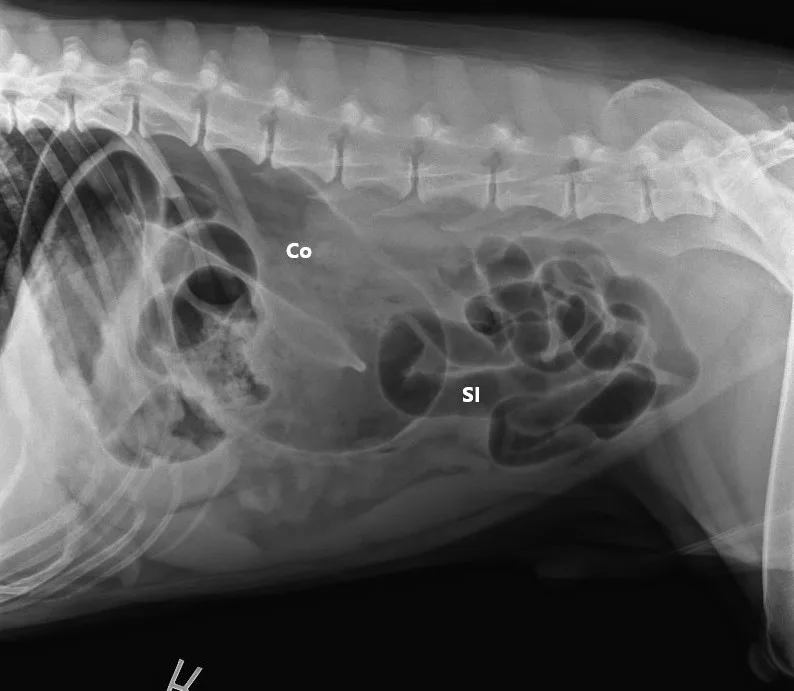

A lubricated 10 French red rubber catheter was inserted rectally and connected to a 60-mL catheter-tip syringe. Air (2 mL/kg) was injected while the anus was occluded by pinching off the anal tissue. Additional 3-view abdominal radiographs revealed normal-diameter, gas-filled small intestines; a markedly gas-distended proximal colon; soft-tissue opacity abnormally located in the right cranial abdomen; and narrowing of the distal lumen of the descending colon (Figure 2). The remainder of the radiographs were unremarkable. Radiographs were assessed by multiple board-certified radiologists, and there was a high index of suspicion for colonic torsion.

FIGURE 1A

Right lateral (A), left lateral (B), and ventrodorsal (C) abdominal radiographs demonstrating marked dilation of a single bowel loop with gas and amorphous material in the right cranial abdomen, suspected to be the colon (arrows). Caudal displacement of the small intestines (SI) can also be seen. The descending colon (Co) is poorly visualized.